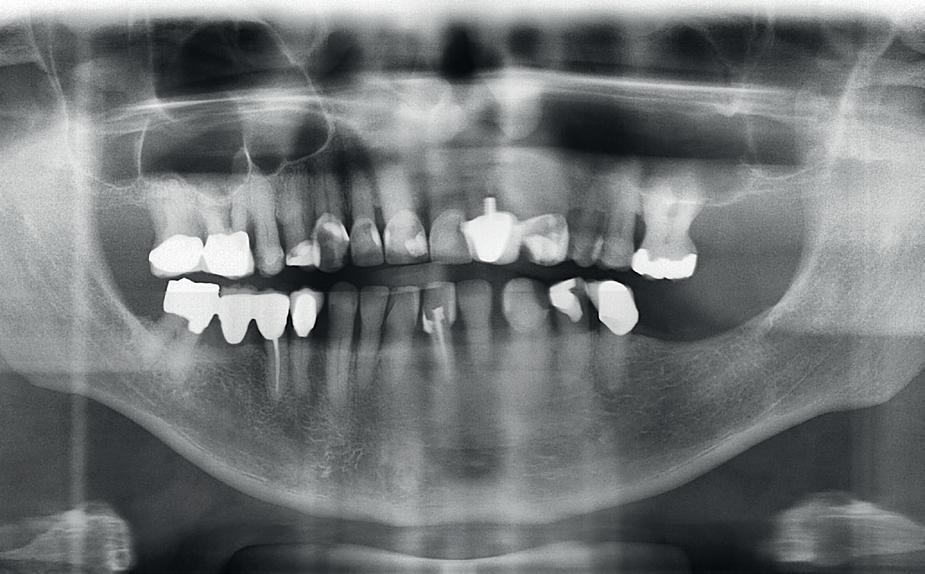

De diagnose luidde lokaal parodontitis met ernstige furcatie aandoeningen; Stadium IV (vergevorderd); graad C (snel progressief) (afbeelding 7) De elementen die niet te behouden waren, werden geëxtraheerd.

Na afronding van de eerste twee behandelstappen werd parodontale stabiliteit bereikt, zoals waarneembaar op de parodontiumstatus en (röntgen)foto’s (afbeelding 6, 8). De patiënt toonde aantoonbare verbetering in mondhygiëne (afbeelding 4) en bleef gemotiveerd om de behandeling voort te zetten.

5. OPT intake